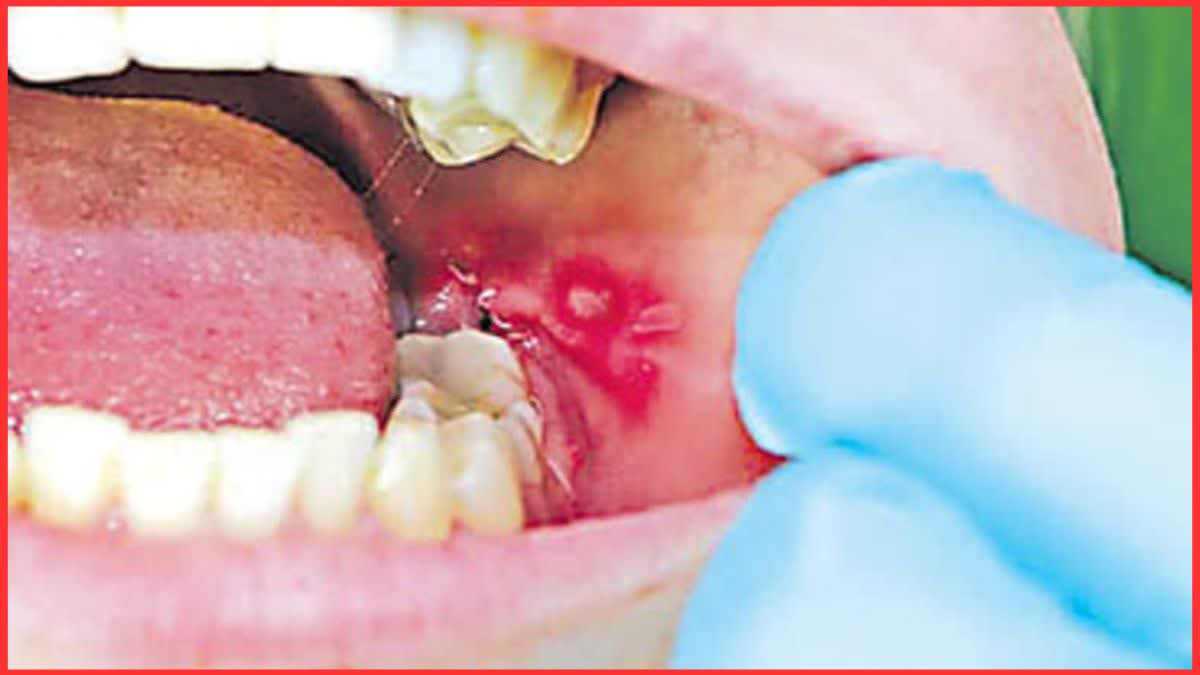

जींद: जिले में ओरल कैंसर के बढ़ते मामलों को देखते हुए स्वास्थ्य विभाग ने इसे रोकने के लिए कमर कस ली है. मुंह के कैंसर को गंभीर सार्वजनिक स्वास्थ्य समस्या मानते हुए विभाग ने जिलेभर में बड़े स्तर पर स्क्रीनिंग, जागरूकता और उपचार की योजना तैयार की है. अधिकारियों का मानना है कि समय पर जांच और सही जानकारी से इस जानलेवा बीमारी को शुरुआती चरण में ही रोका जा सकता है.

स्वास्थ्यकर्मियों को दी जाएगी विशेष ट्रेनिंग: स्वास्थ्य विभाग की योजना के तहत जिले के सभी स्वास्थ्यकर्मियों को ओरल कैंसर की पहचान, रोकथाम और प्राथमिक उपचार को लेकर विशेष प्रशिक्षण दिया जाएगा. इस ट्रेनिंग में मुंह के कैंसर के शुरुआती लक्षण, जांच की प्रक्रिया और संदिग्ध मरीजों को समय पर रेफर करने की जानकारी दी जाएगी. इससे प्राथमिक स्वास्थ्य केंद्रों से लेकर जिला अस्पताल तक स्क्रीनिंग व्यवस्था को मजबूत किया जाएगा.

मेगा कैंपों में जांच के साथ उपचार भी: ओरल कैंसर की रोकथाम के लिए जिले में जल्द ही मेगा स्क्रीनिंग कैंप लगाए जाएंगे. इन कैंपों में लोगों की मुंह की जांच की जाएगी और संदिग्ध मामलों में तुरंत उपचार शुरू किया जाएगा. जरूरत पड़ने पर मरीजों को उच्च चिकित्सा संस्थानों में रेफर भी किया जाएगा. विभाग का लक्ष्य है कि बीमारी को शुरुआती स्टेज में पकड़कर इलाज को आसान और प्रभावी बनाया जाए.

70 प्रतिशत कैंसर मरीज मुंह के कैंसर के: नागरिक अस्पताल के डिप्टी सीएमओ डॉ. रमेश पांचाल ने चौंकाने वाला आंकड़ा साझा करते हुए बताया कि, "कैंसर जांच के लिए आने वाले मरीजों में करीब 70 प्रतिशत मामले मुंह के कैंसर के सामने आ रहे हैं. इसका सबसे बड़ा कारण तंबाकू सेवन है, जिसमें बीड़ी, सिगरेट, पान, सुपारी, गुटखा, खैनी और जर्दा शामिल हैं."